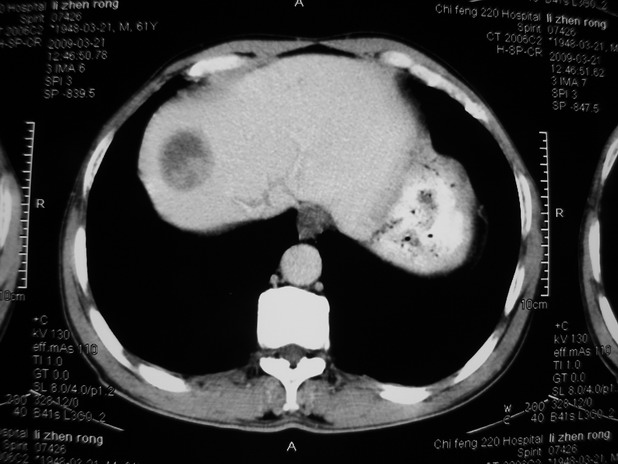

以下是引用余辉在2009-3-21 21:36:00的发言:[br]图像太乱了,建议楼主直接将强化数据按顺序列出来,病灶位置较表浅薄,有肝炎病史,灶内实性成分有显著强化,动脉期约60hu,考虑肝癌可能性大,进一步检查。